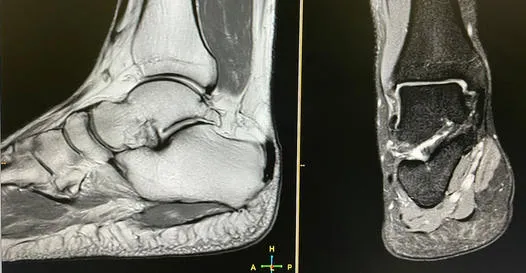

Tomografia komputerowa i rezonans magnetyczny: kiedy potrzebna jest głębsza analiza?

W przypadku wątpliwości po badaniu RTG lub podejrzenia poważniejszych uszkodzeń, niezbędne stają się bardziej zaawansowane badania. Tomografia komputerowa (TK) pozwala na dokładniejszą ocenę struktury kostnej, wykrywając nawet drobne złamania czy przemieszczenia. Rezonans magnetyczny (MRI) natomiast jest niezastąpiony w ocenie tkanek miękkich więzadeł, torebek stawowych i chrząstek. Dzięki niemu możemy precyzyjnie określić zakres uszkodzenia więzadeł Lisfranca, co jest kluczowe dla wyboru metody leczenia.

Precyzyjna diagnostyka ma ogromne znaczenie w odróżnieniu skręcenia śródstopia od złamania czy zwichnięcia. Każdy z tych urazów wymaga innego podejścia terapeutycznego. Skręcenie to uszkodzenie więzadeł, złamanie to przerwanie ciągłości kości, a zwichnięcie to utrata kontaktu powierzchni stawowych. Badania obrazowe, zwłaszcza TK i MRI, są kluczowe w tej różnicowaniu, pozwalając na postawienie trafnej diagnozy i wdrożenie najskuteczniejszego leczenia.